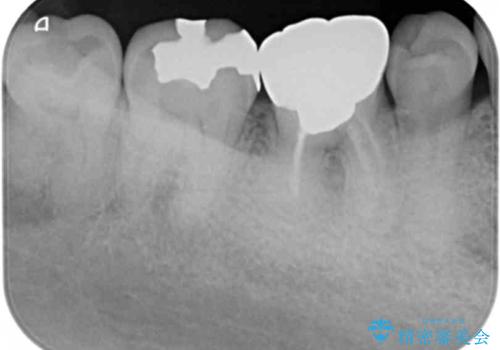

- 長年気になっていた、目立つ銀歯を白くしたい。とセラミック治療を希望され来院されました。

銀歯を除去したのち、精度の良いジルコニアセラミッククラウンでクラウンのやり替えを行っていきます。